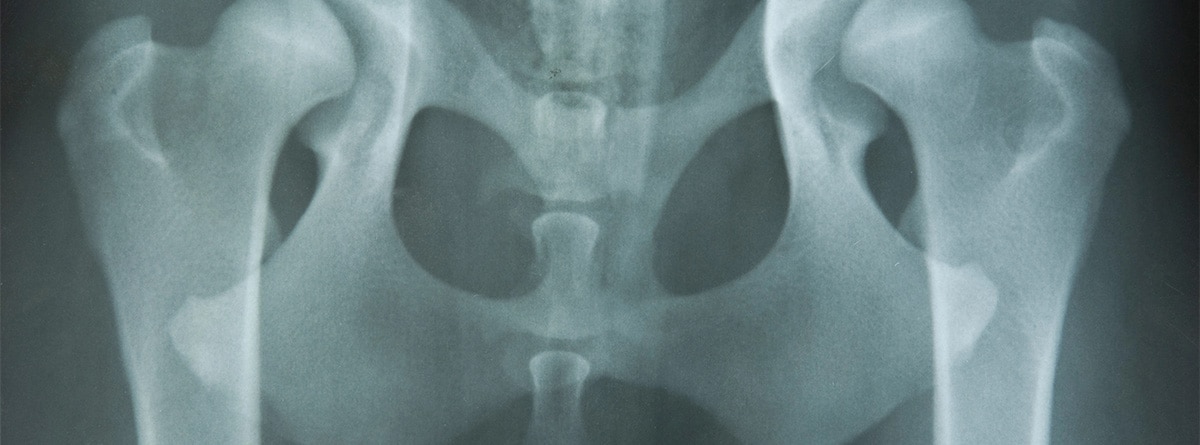

La displasia fibrosa es una enfermedad ósea rara que puede afectar uno o varios huesos del cuerpo. Se caracteriza por el reemplazo anormal del tejido óseo normal por un tejido fibroso, lo que puede debilitar los huesos y provocar deformidades. Aunque es una condición benigna, en algunos casos puede generar complicaciones significativas, como fracturas o problemas de movilidad. Este es un trastorno óseo no hereditario que ocurre cuando un error genético provoca el crecimiento desorganizado del hueso. En lugar de desarrollar un hueso normal y fuerte, el cuerpo forma un tejido fibroso inmaduro, lo que da lugar a debilidad estructural.

- Deformidades óseas: los huesos afectados pueden volverse curvados o engrosados, especialmente en los huesos largos (fémur, tibia, húmero).

- Fracturas espontáneas: Debido a la debilidad estructural del hueso, las fracturas pueden ocurrir con traumatismos mínimos.